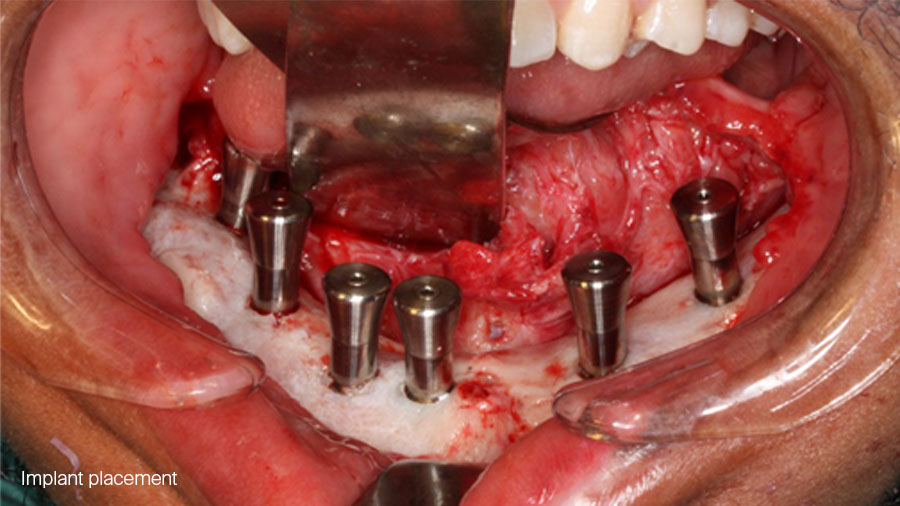

6 months later ossicle maturation is complete and planning and execution of implant placement can be done in the traditional manner.